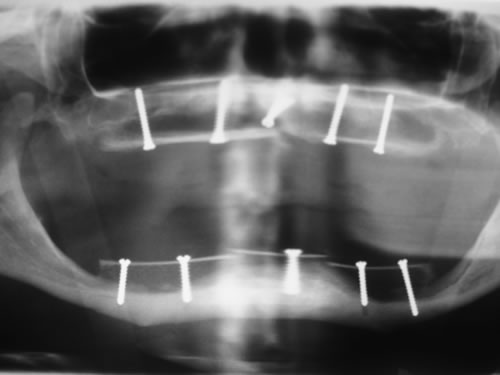

Bei der ersten Untersuchung in der Praxis hat Frau W. zunächst den Anamnesebogen ausgefüllt. Sie ist nie ernstlich krank gewesen und nimmt nur gelegentlich eine Kopfschmerztablette. In einem ausführlichen Gespräch berichtet sie ihrem Zahnarzt über die Schwierigkeiten mit den Prothesen. Nach einer ersten Untersuchung kann ihr der Zahnarzt Mut machen. Die Kieferverhältnisse sind zwar sehr ungünstig, doch so, dass eine Einpflanzung noch möglich ist. Die vorhandenen Prothesen weisen keine Mängel auf, finden aber keinen Halt. Beide Prothesen sollen nach der Einpflanzung weiter getragen werden. Nach einem Kieferabdruck wird eine Platte für den Unterkiefer angefertigt, auf der Metallkugeln befestigt sind. Sie wird wie eine Prothese eingesetzt, und es wird eine Röntgenaufnahme gemacht, die anschließend vom Zahnarzt genau vermessen wird. Es ergibt sich, dass noch eine Resthöhe von 15 mm vorhanden ist. Da auch die Breite des Kiefers ausreicht, wird ihr die Einpflanzung von vier künstlichen Zahnwurzeln empfohlen. Für ihre spezielle Kieferform ist dies die beste Lösung.

Für den Oberkiefer ist eine CT-Untersuchung notwendig, die ebenfalls mit einer Schablone durchgeführt wird. Auswertung, Planung und Implantations-Simulationen ergeben, dass sechs Implantate im vorderen Kieferabschnitt verankert werden können. Auch die Qualität des Knochens lässt eine Einpflanzung ohne weitere Maßnahmen zu. Diese Behandlung soll nach der Versorgung des Unterkiefers erfolgen.